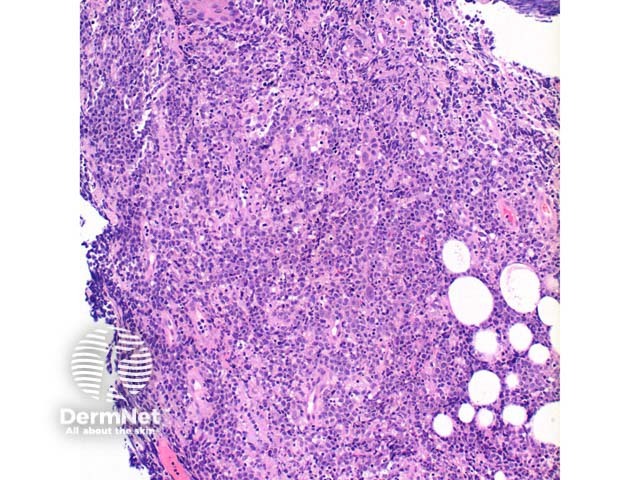

Scanning power view of the histology of primary cutaneous diffuse large B cell lymphoma is of a dense superficial and deep cellular infiltrate (figure 1). Higher power identifies a dense atypical lymphocytic proliferation, which frequently extends into the subcutaneous tissue (figures 2, 3, 4, 5). Areas of crush artefact are common, and while not specific may be a clue to a malignant lymphoid population (figures 2, 3). The lymphocytes are large centroblast-like and immunoblast-like cells with non-cleaved nuclei and prominent nucleoli (figure 6, 7).

Figure 2

Figure 3